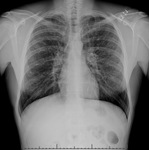

Radiografía de tórax que muestra la hiperinflación en un paciente con EPOC. El tórax distendido es causado por el componente enfisema de la EPOC, en lugar de por la bronquitis crónica, que subyace los síntomas de tos

De la colección personal del Dr. M. A. Sharifabadand, SUNY en Stony Brook School of Medicine, Departamento de Medicina Intensiva y Pulmonar, Mineola, Nueva York y el Dr. J. P. Parsons, The Ohio State University Medical Center, Columbus; usado con autorización